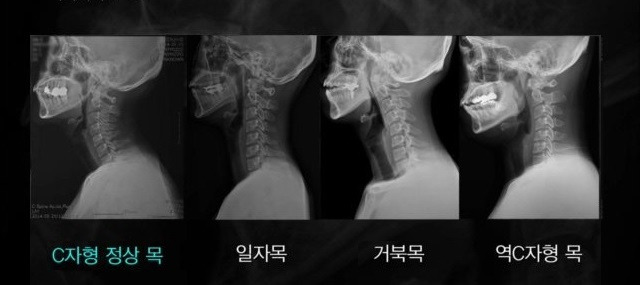

증상 단계는 총 세 단계로 나눠볼 수 있다. 첫째로 가장 정상인 C자형 목, 둘째로 일자목, 셋째로 거북목이다. 증상이 심한 거북목은 역 C자형 목이 된다.